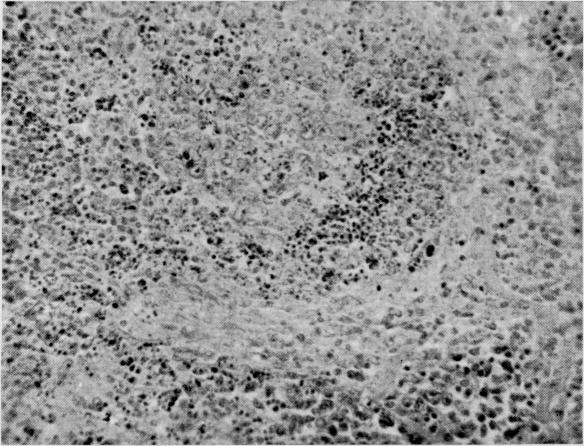

A correlation of early radiation changes in lymphatic tissues with antitoxin-producing ability.

https://cdn.ncbi.nlm.nih.gov/pmc/blobs/e7e5/2599747/c07b08e7e1a8/yjbm00307-0042-a.jpg